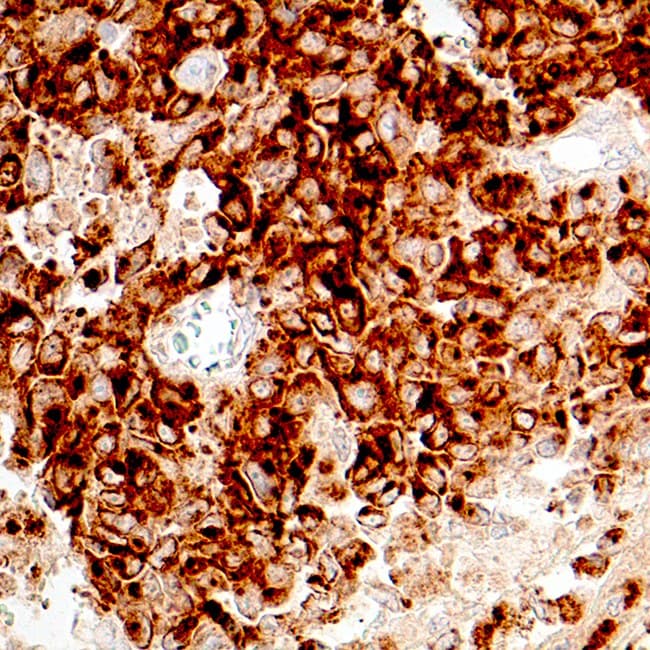

Sección de melanoma